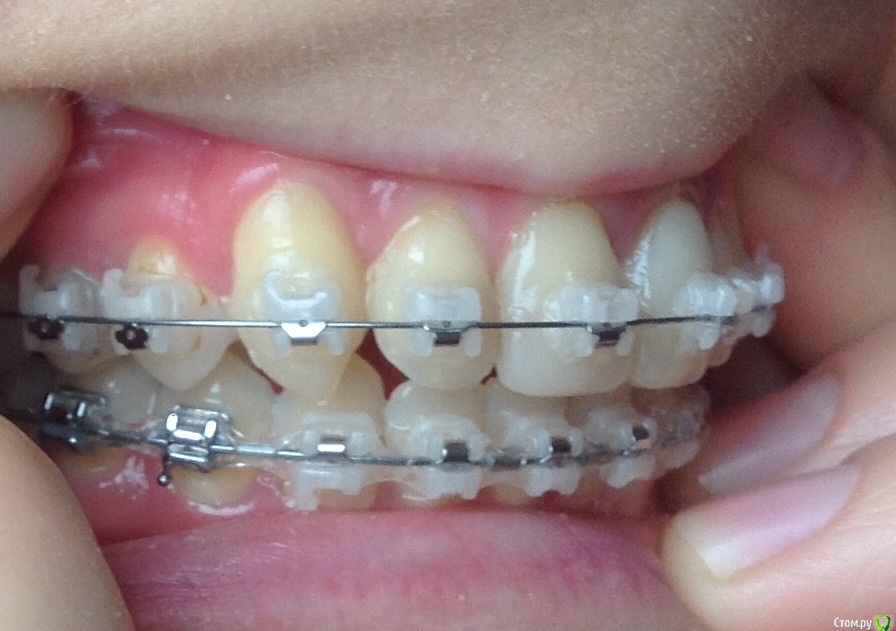

Добрый день ! Мне 29 лет. Ношу брекеты 10 мес. На данном этапе лечения сделали панорамный снимок, чтобы посмотреть ровно ли стоят корни зубов. После этого врач решил переклеить один брекет на клыке ( на снимке его видно слева ). А мне по снимку бросились в глаза , помимо этого клыка, рядом стоящий боковой резец ( он же не нравится мне как стоит и внешне) , и на нижней челюсти : 1- ый премоляр,и рядом стоящие 3 резца. Врач сказал подумать неделю и решить, хочу ли я переклеить или нет какой либо из брекетов,тк дальше они так и останутся. На её взгляд ничего переклеивать , кроме клыка, больше не нужно.

П.с. На нижн. челюсть уже поставили резинки для стягивания щелей. Я так понимаю после этого этапа уже на них брекеты не будут переклеиваться ?

Главный вопрос : Нужно ли мне переклеивать еще какие- нибудь брекеты , опускать или поднимать какой- либо из зубов, чтобы добиться большей эстетики и в дальнейшем правильного прикуса ? Или же не нужно. Заранее спасибо за внимание.